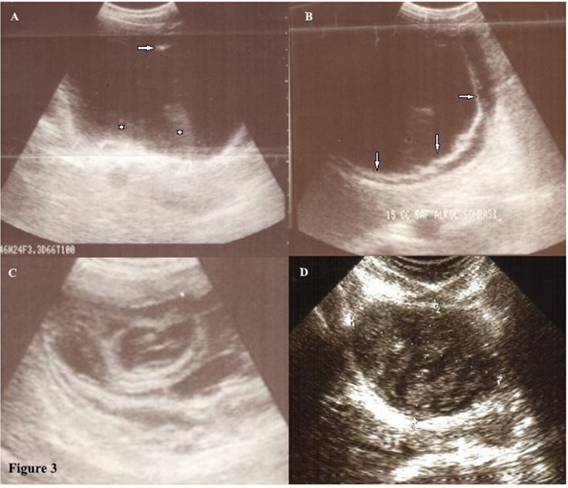

The patients were evaluated by detachment, perforating and color changing of the germinative membrane, reduction of cyst volume; degeneration, solidification and calcification of the cysts on the ultrasound examination during and one day after the procedure. The germinative membrane of some of the cysts (46.7%) was detached from the cyst wall, became white, were torn apart and went to pieces down in the type of CE 1 and CE 3A (Figure 3) at the time of the treatment. The CE 2b, 2c and 3B cysts degenerated, changed color and some of the germinative membrane of daughter cysts were detached. They became smaller (87.7%) and 21 (3.9%) of the cysts disappeared. They solidified (91.0%) and calcified (15.4%) during the follow-up (Figures 4). Interestingly, 47 cysts in 36 patients were affected by the treatment of another cyst. They resulted in degeneration and they finally died (Figure 5). Blood samples were collected to check CBC, sedimentation rate, ALT; AST, alkaline phosphatase, GGT and bilirubin before and after the procedure for all patients. The mean follow-up time was 51.24±62.99 (minimum 3.00, maximum 340.00) months. The treatment was effective. (Table 1) When the treatment was not efficient on the first puncture, a second [-n=53(9.9%)], third [-n=8(1.5%)-] and fourth puncture [-n=2(0.4%)-] were applied during the follow-up. Forty-seven (9.91%) out of 474 patients applied to us with several complications before the treatment due to HD. Of 474 patients, 42 (8.86%) had some complications after the treatment. (Tables 2 & 3)

Figure 3 Eight-year-old girl with hydatid cyst (stage CE type 1 according to WHO classification).

(A) Before the percutaneous treatment, there is an anechoic cyst with fine internal echoes representing the ‘hydatid sand’ (asterisks), the arrow shows the needle tip.

(B) The germinative membrane (arrows) detached right after the treatment.

(C) The onionskin pattern is seen in the solidified hydatid cyst after a few months of treatment.

Absolutely solidified hydatid cyst (stage CE type 4 according to WHO classification) seen 27years after the treatment.